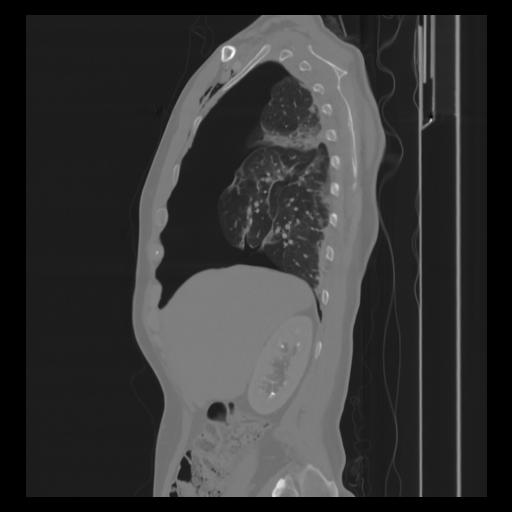

30 CUERPO,CE,Sagittal,3.000,CUERPO,Sagittal,